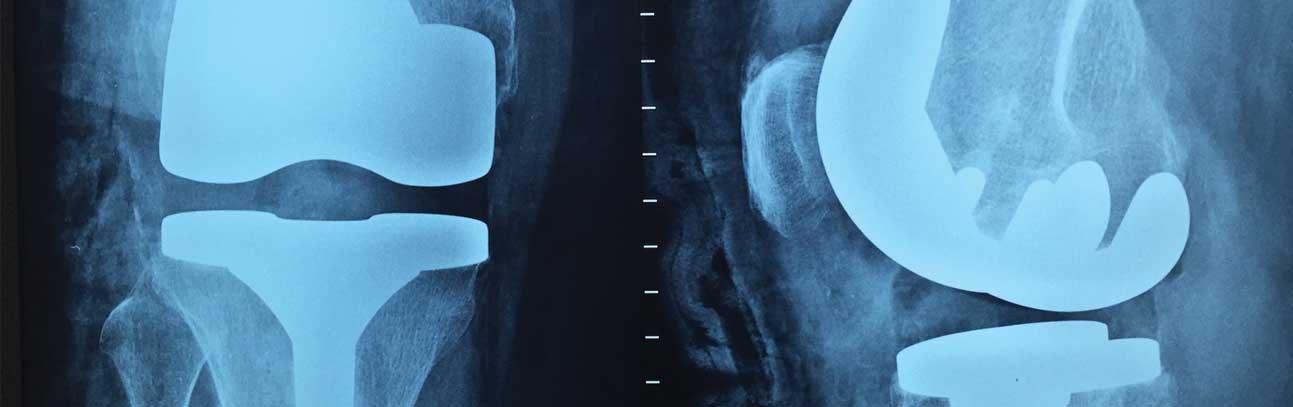

Your Houston-Based Defective Knee Replacement Lawyers

Knee replacement surgery is rather common. But, sadly, knee replacement lawsuits happen just as frequently. The number of patients who require surgery because of defective artificial knees has doubled in the last ten years.

Defective Knee Replacement Devices and Their Expensive, Painful Complications

Patients with faulty or failed knee replacement devices suffer a variety of medical issues, which can include the following: